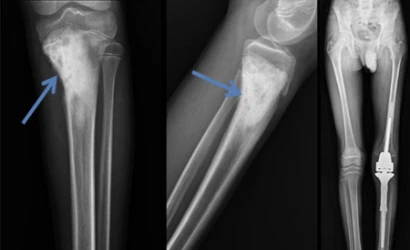

OSTEOKONDROM

Osteokondrom Nedir ?

Osteokondrom, kemik ve kıkırdak dokunun kemik yüzeyinden dışarı doğru büyümesiyle oluşan iyi huylu (be...